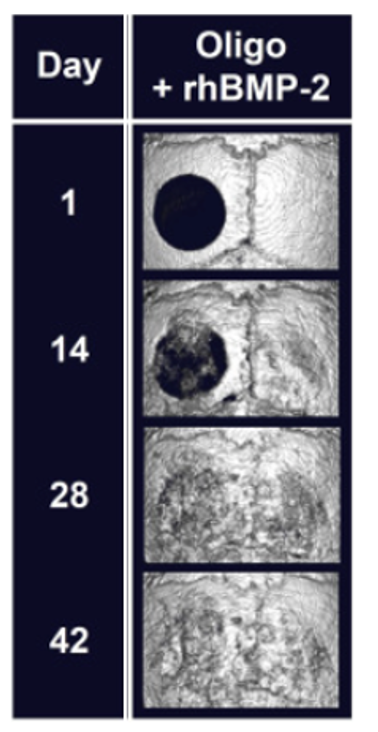

Development Opportunity 2: Tendon Healing and Adhesion Prevention

Traditional methods fall short of fully regenerating severed tendons. Our Tetra-Gel (hydrogel) barrier material, however, offers a novel solution by preventing external cell invasion and adhesion, thereby facilitating only intrinsic healing. We are progressing with both non-clinical and clinical trials to bring this technology to market and are looking for development partners to join us in this endeavor.